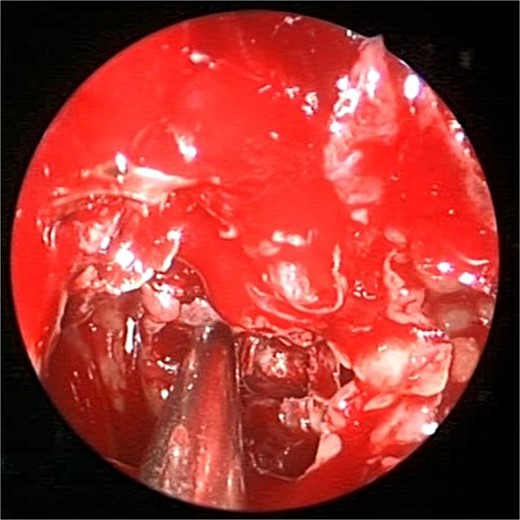

A 36 years-old man with no previous history of medical disease presented to the otolaryngology clinic with a chief complaint of headache that was associated with pressure feeling mainly in the occipital area. He also reported a post-nasal drip. The patient underwent a non-contrast paranasal sinus CT scan (Fig. 1) that demonstrated an isolated sphenoid sinus homogenous opacification, most likely representing sphenoid fungal ball. A decision was made to proceed with endoscopic sphenoidotomy (Fig. 2) to clean and remove the debris, which confirmed the diagnosis of sphenoid sinus fungal ball.

Intra-operative (A and B) endoscopic sphenoidotomy showing fungal debris, with post-operative examination (C) showing clean wide sphenoid sinus free from fungal debris.